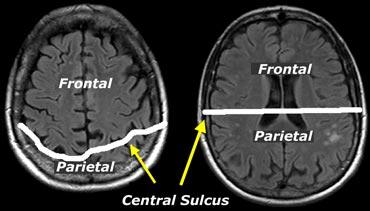

Khi đánh giá mức độ teo não ở các vùng khác nhau, cần lưu ý rằng ở phía đỉnh đầu, rãnh trung tâm nằm ở vị trí sau hơn so với dự kiến (hình minh họa).